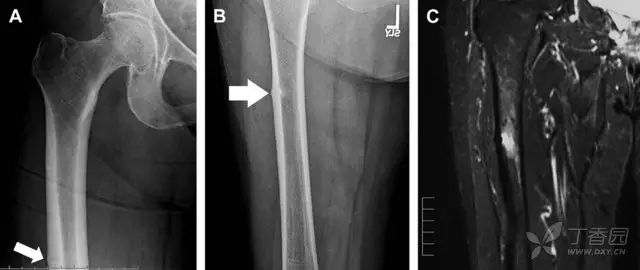

另一种易漏诊的骨折是非典型股骨骨折,这种骨折与长期服用双膦酸盐相关,常发生在使用双膦酸盐 3 年以上的患者。前驱症状表现为腹股沟痛或大腿痛的患者中,60%~70% 被错误地认为由腰背痛或髋关节炎引起。

这种骨折的一个典型表现为火山口状骨膜隆起及一横行透亮带。值得注意的是,超过 50% 的患者表现为股骨干完全骨折。由于 50%~60% 的患者会累及双侧,所以一旦一侧下肢确诊,需行对侧下肢检查。

图 10 老年患者长期服用双磷酸盐引起的骨折。A 髋部正位片,箭头所示,股骨外侧皮质存在横行透亮带。B 后续的股骨 X 线片示局灶性骨膜反应,以及此类骨折的特征性表现-火山口状骨膜隆起(箭头)。C MRI 冠状位 STIR 序列扫描示相应骨折平面的骨髓水肿表现